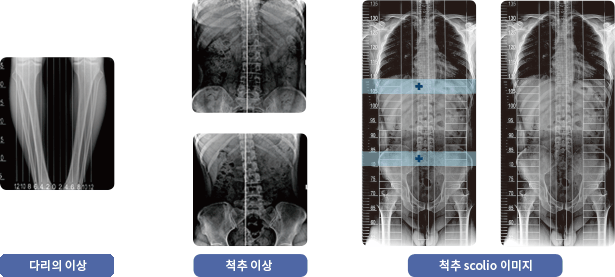

• 다리 정보

SCOLIO를 이용한 다리의 휨 정도를 구분할 수 있습니다. 수술전후 Lead Line이 새겨진 방사선영상은 정밀한 진단을 유도합니다.

• 골반 정보

SCOLIO를 이용한 골반의 수평정도를 알 수 있습니다.

방사선 영상의 조합을 실측 사이즈로 정밀하게 조합가능

방사선 영상의 이미지를 최소로 간섭하며 진단의 정확성을 살려주는 리드라인